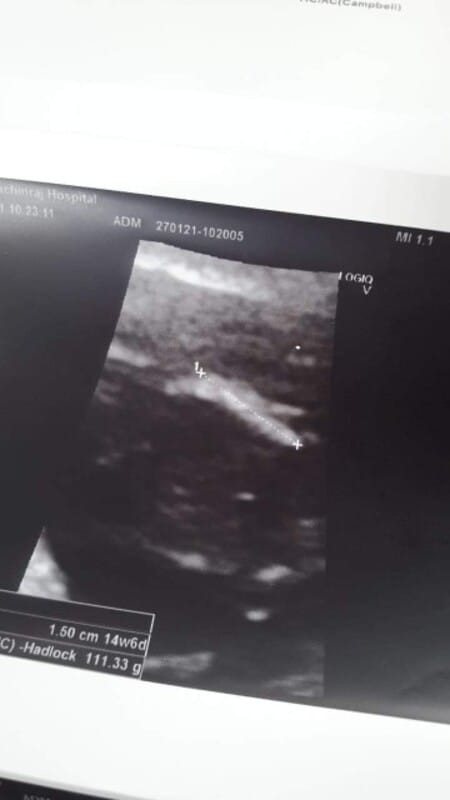

หมอบอกได้ผ.ชจ้ะ

แบบนี้ได้ผ.ชจริงมัยค่ะ🙂😅#ขอคำแนะนำหน่อยค่ะ